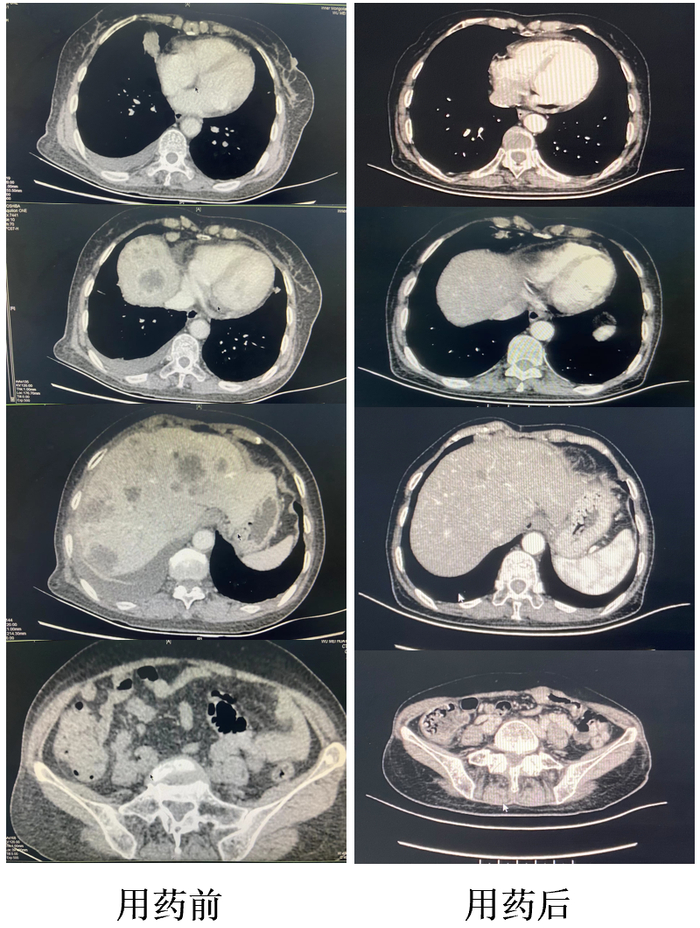

2.达拉非尼+曲美替尼一线治疗,肺部病灶CR,腹部病灶PR

2023年4月,腹部增强CT复查结果显示:考虑肝内多发转移瘤,与本院2022年8月19日CT对比较前减少、部分减少,部分增大。肝S4段低密度结节,较前无明显变化。右侧心隔角、肠系膜区、腹膜后多发肿大淋巴结,考虑转移。回盲部肠系膜区不规侧软组织结节,考虑转移,较前减少。疗效评估为PR。

2023年4月,肺部CT复查结果显示:双肺多发微小结节,部分磨玻璃密度,细支气管炎,支气管炎性改变。疗效评估为CR。

患者经保肝等对症治疗后,肝功能明显改善,食欲恢复,一般状态良好,ECOG PS 0分。靶向治疗后整体治疗效果评估为PR。患者无不适症状,医嘱继续口服达拉非尼+曲美替尼及保肝药,出院定期复查。